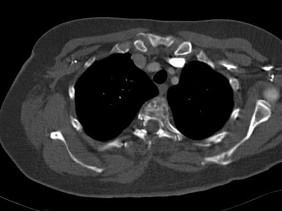

问题 女,47岁,背痛半月余,2个月前被诊断为乳腺癌肝转移,请结合影像学检查,选出最可能的诊断 ( )

选项 A、椎体压缩骨折 B、脊椎退行性变 C、脊椎转移瘤 D、化脓性脊柱炎 E、脊椎结核

答案 C